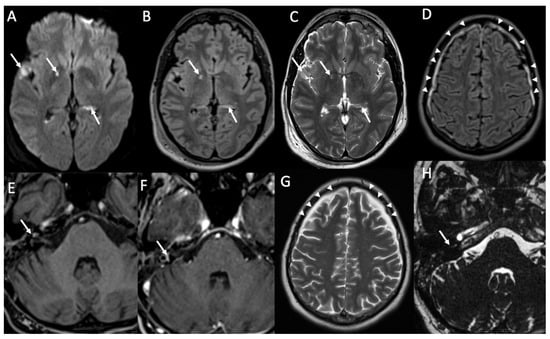

| Piogenic Meningitis | • Cerebrospinal fluid hyperintensity in T1 and FLAIR • Restricted diffusion of the subarachnoid spaces • Meningeal enhancement on T1 and FLAIR |

| Herpes Virus type 1 | • Mesio-temporal involvement • Bilateral and asymmetric pattern • Cortical hyperintensity on T2 and FLAIR, with restricted diffusion (acute phase) and cortical enhancement (subacute phase) • Hemorrhagic foci |

| Varicella Zoster Virus | • Leptomeningeal enhancement • Cerebellitis |

| Cytomegalovirus | • Hyperintense areas in T2 and FLAIR in the periventricular white matter • Ventriculitis |

| Human herpesvirus type 6 | • Similar to herpes virus type 1, but cortical enhancement is more common |

| West Nile virus | • Hyperintensity in T2 and FLAIR of basal ganglia, thalami and midbrain |

| Enterovirus | • Rhombencephalitis |